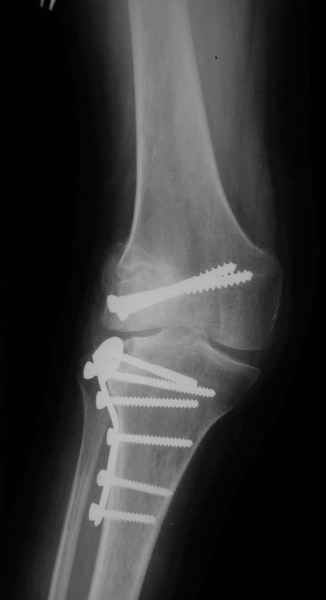

Уважаемые коллеги!На прием обратилась больная 38 лет. Травма 17.01.2005. 23.01.2005 - операция в одном из стационаров области - остеосинтез мыщелка бедра винтами, Остосинтез мыщелка большеберцовой кости L-образной пластиной.

Остальные снимки Ноябрь 2005

Иммобилизация лонгетной гипсовой повязкой 2 мес. После прекращения иммобилизации, пр начале ЛФК отмечена нарастающая вальгусная деформация конечности. Рентгенограммы в приложении. Хотелось бы узнать Ваши предложения по тактике лечения

Уважаемый Евгений ! Спасибо за ответ, но мне представляется, что в нашем случае основной проблемой является не столько прогрессирующий вальгус конечности, сколько несросшийся перелом мыщелка бедра и дефект мыщелка большеберцой кости - вероятно первичная репозиция выполнялась без пластики.

Мне представляется, что прогрессирующий вальгус и обусловлен несросшимся переломом мыщелка бедра (томограммы -зона межфрагментарного склерозирования), а циклические нагрузки на сустав во время ходьбы усугубляют ситуацию. Как вы думаете, в этой ситуации насколько вероятен риск развития аваскулярного некроза мыщелка бедра?